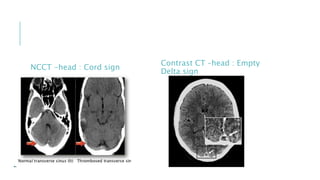

NCCT -head : Cord sign

Contrast CT –head : Empty

Delta sign

NCCT -head :Cord sign Contrast CT –head : Empty Delta sign